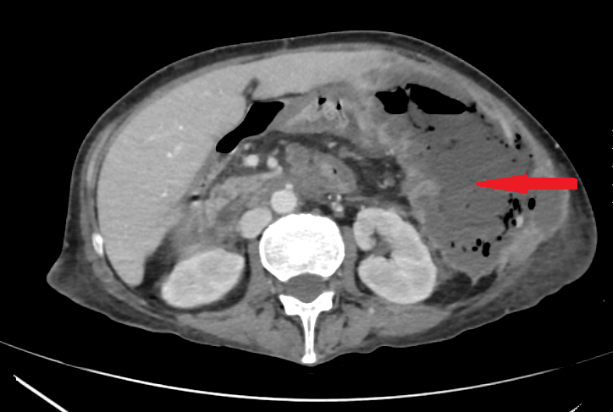

Red arrows – Rectal stromal tumor. Multiple liver metastases (Courtesy Dr. V. Penopoulos)